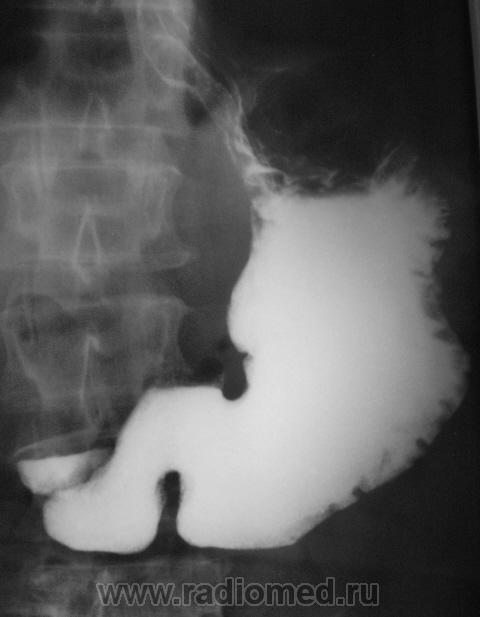

Пациент, который длительное время находился на диспансерном учете, как "язвенный больной", в последние годы не обследовался. Отмечает, что болей не ощущает, но очень резко похудел за последние два года.

нехорошая язва, уже может быть и инфильтративно-язвенные рак, биопсию надо делать

Ригидность контуров всего тела желудка, центральный дефект наполнения в теле, изьязвление по малой кривизне, кисетообразная деформация всего желудка - убедительные признаки обширного опухолевого поражения.